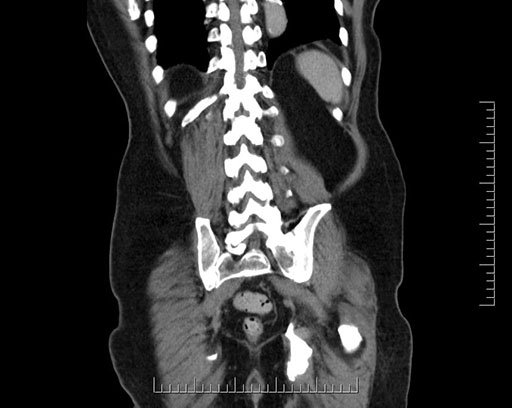

Whipple (pancreaticoduodenectomy) [case 7]

Imaging Analysis

Look through the patient's CT scan to identify any areas of concern for the necessary procedure.

Coronal - stented